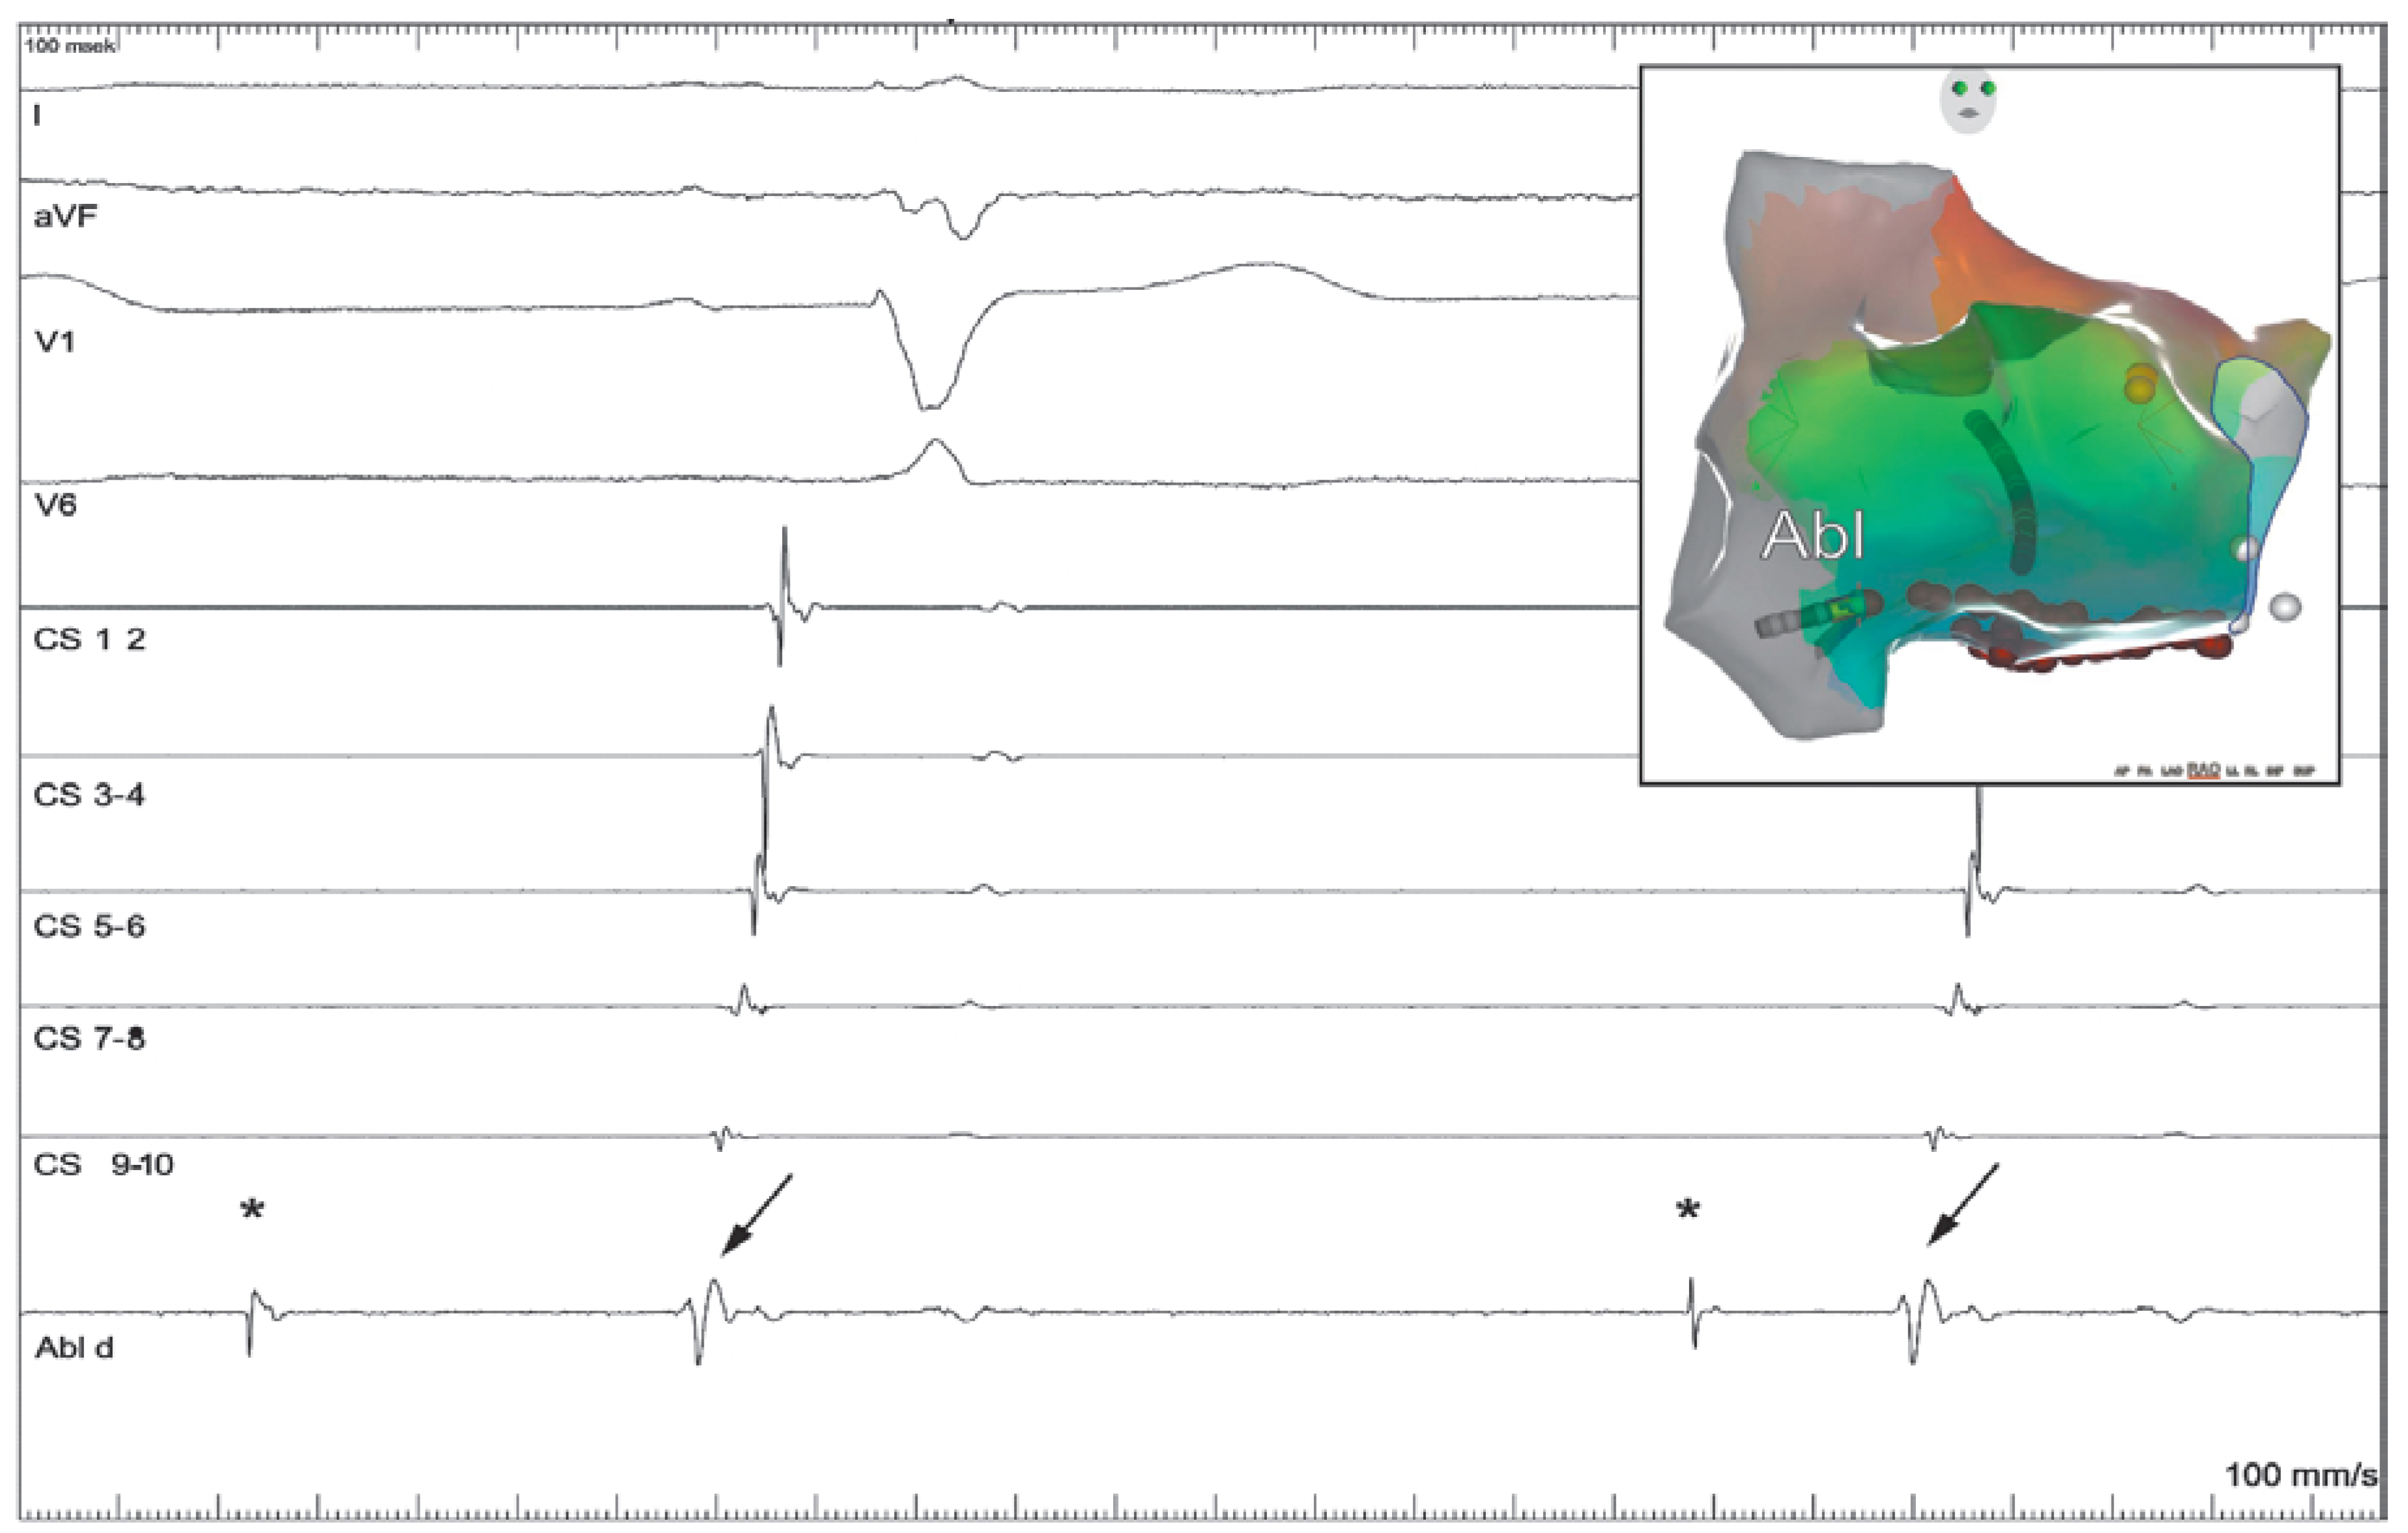

Case report